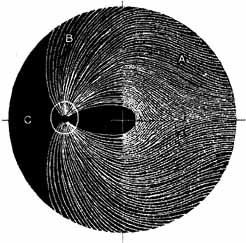

ANATOMY Orbit The orbital apex has two major openings, the orbital fissure and the optic canal (Fig. 1). The orbital fissure is divided into a superior and inferior portion by the tendon of Zinn, the inferior insertion for the tendinous anulus of Zinn (Fig. 2).1,4 (The anulus of Zinn is completed by the origins of the rectus muscles and the superior tendon of Lockwood.) Structures emanating through the optic canal (the optic nerve, ophthalmic artery, and orbital sympathetic nerves) as well as some structures coursing through the superior orbital fissure (the superior and inferior branches of the oculomotor nerve (cranial nerve III), the abducens nerve (cranial nerve VI) and the nasociliary branch of the ophthalmic division (cranial nerve V1) of the trigeminal nerve pass through the anulus of Zinn.